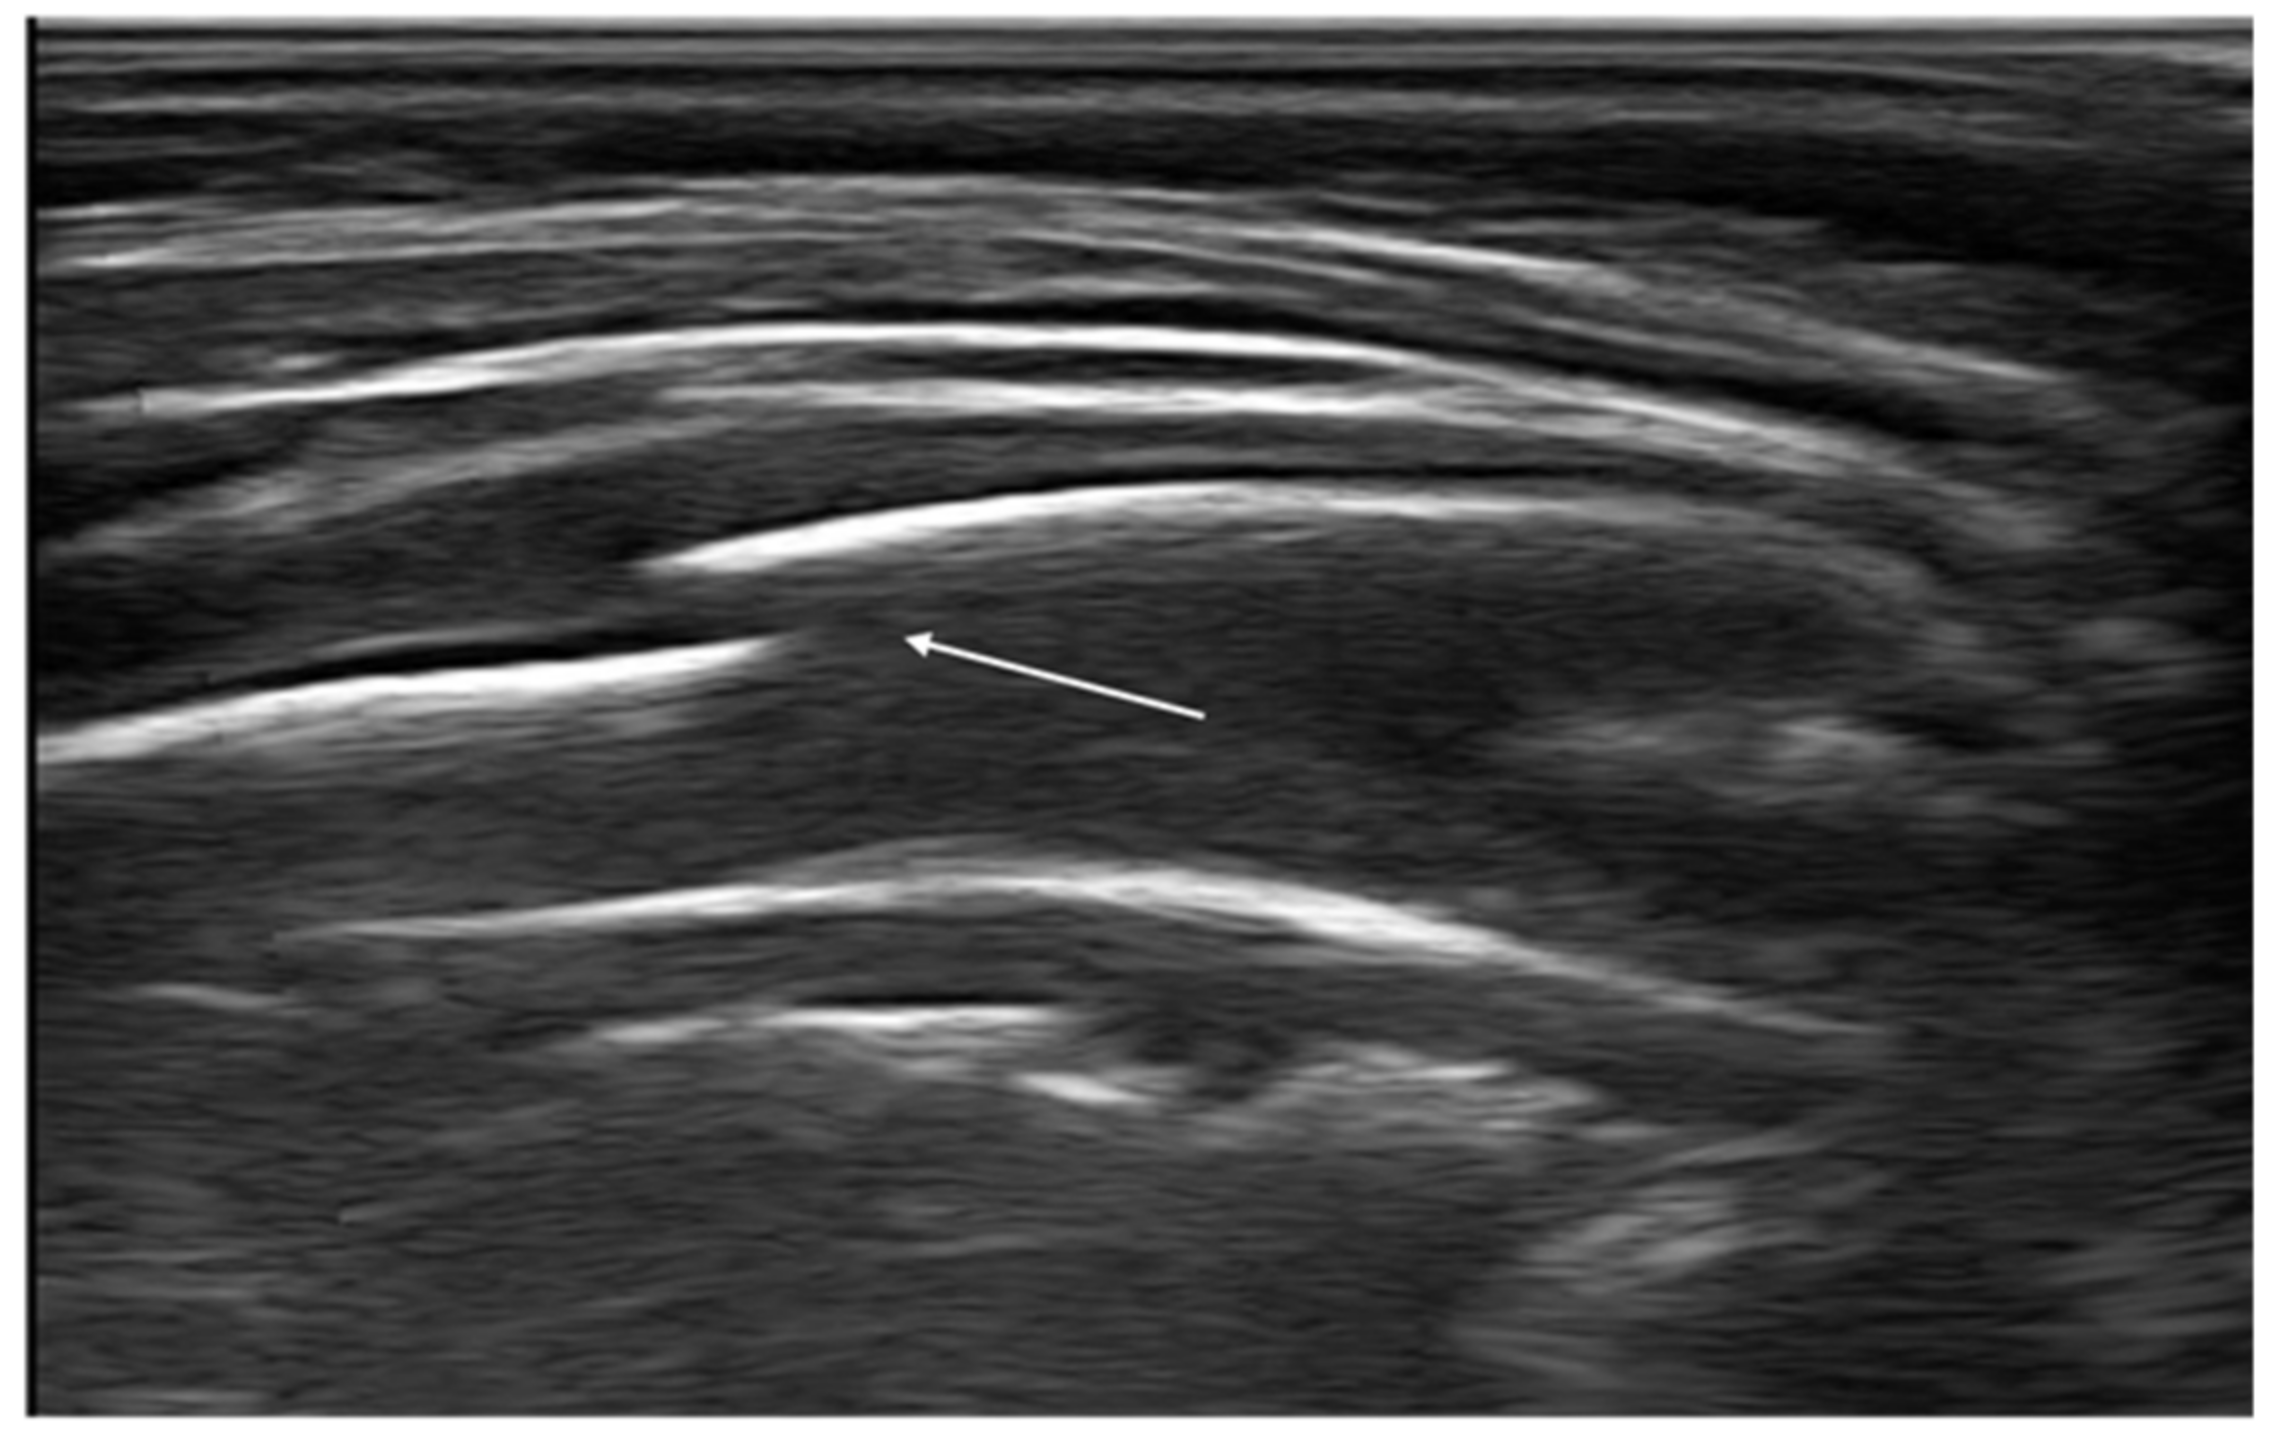

“A-lines” represent some of these artifacts that can be found in a completely healthy lung (Figure 1) [14]. They are horizontal echogenic lines equidistant and parallel to each other and the pleura, representing reverberations of the pleura itself that arise when the ultrasound beam reflects off of the pleura and partially reflects off of the probe face back to the pleura again before getting back to the machine instead of entering the probe. They are caused by the large difference in acoustic impedance between the pleura and the air contained in the lungs. The distance from each other is related to the distance between the pleural line and the skin surface, and their position does not change with respiratory acts.

Appearance of a healthy lung. White arrows show pleural and A-lines.